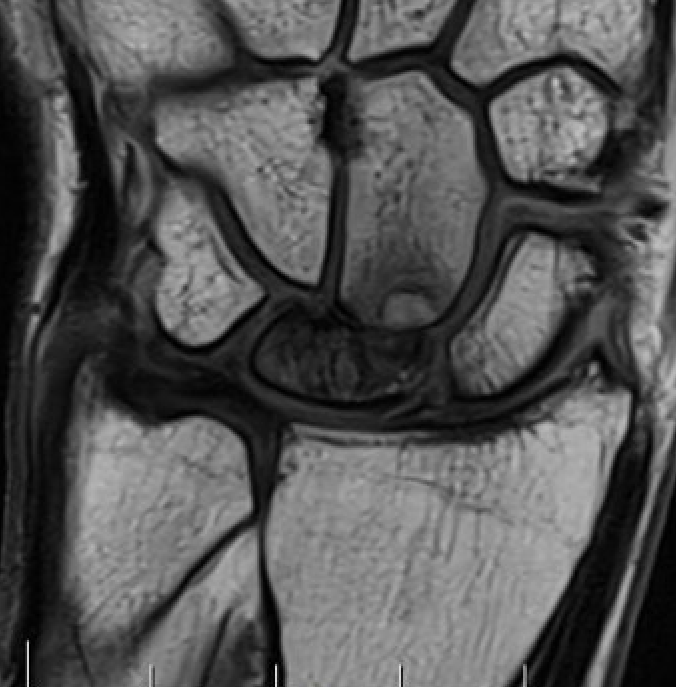

MRI

Avascular lunate on MRI